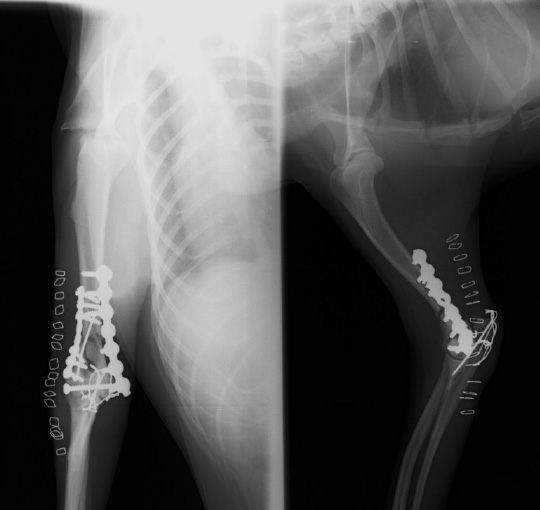

|

左のレントゲン画像は手術前には脛骨近位の高平部が尾側かつ遠位に傾斜しています。

術前計画にて使用するインプラントのサイズや回転角度を計測しています。 |

右のレントゲン画像は手術後の画像です。

脛骨近位高平部が回転し水平化しています。これにより膝関節が安定化し、症状が改善します。 |